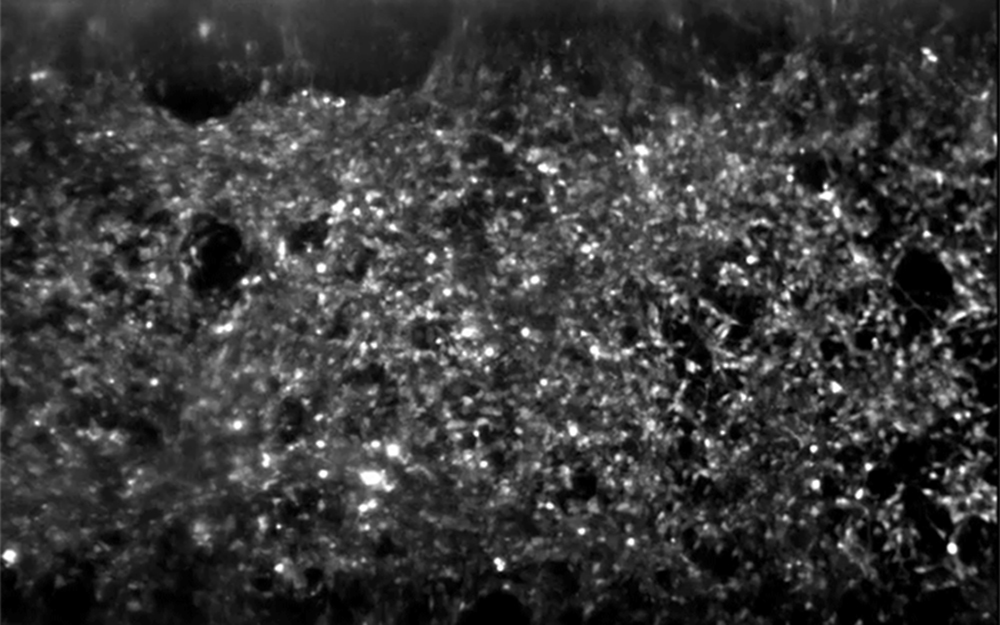

Hundreds of spinal motor neurons spontaneously communicate through electrical signals inside an Organ-Chip. Neurons fire individually (flashing dots) and in synchronized bursts (bright waves). The activity was observed using a dye that fluoresces when neurons send an electrical signal.